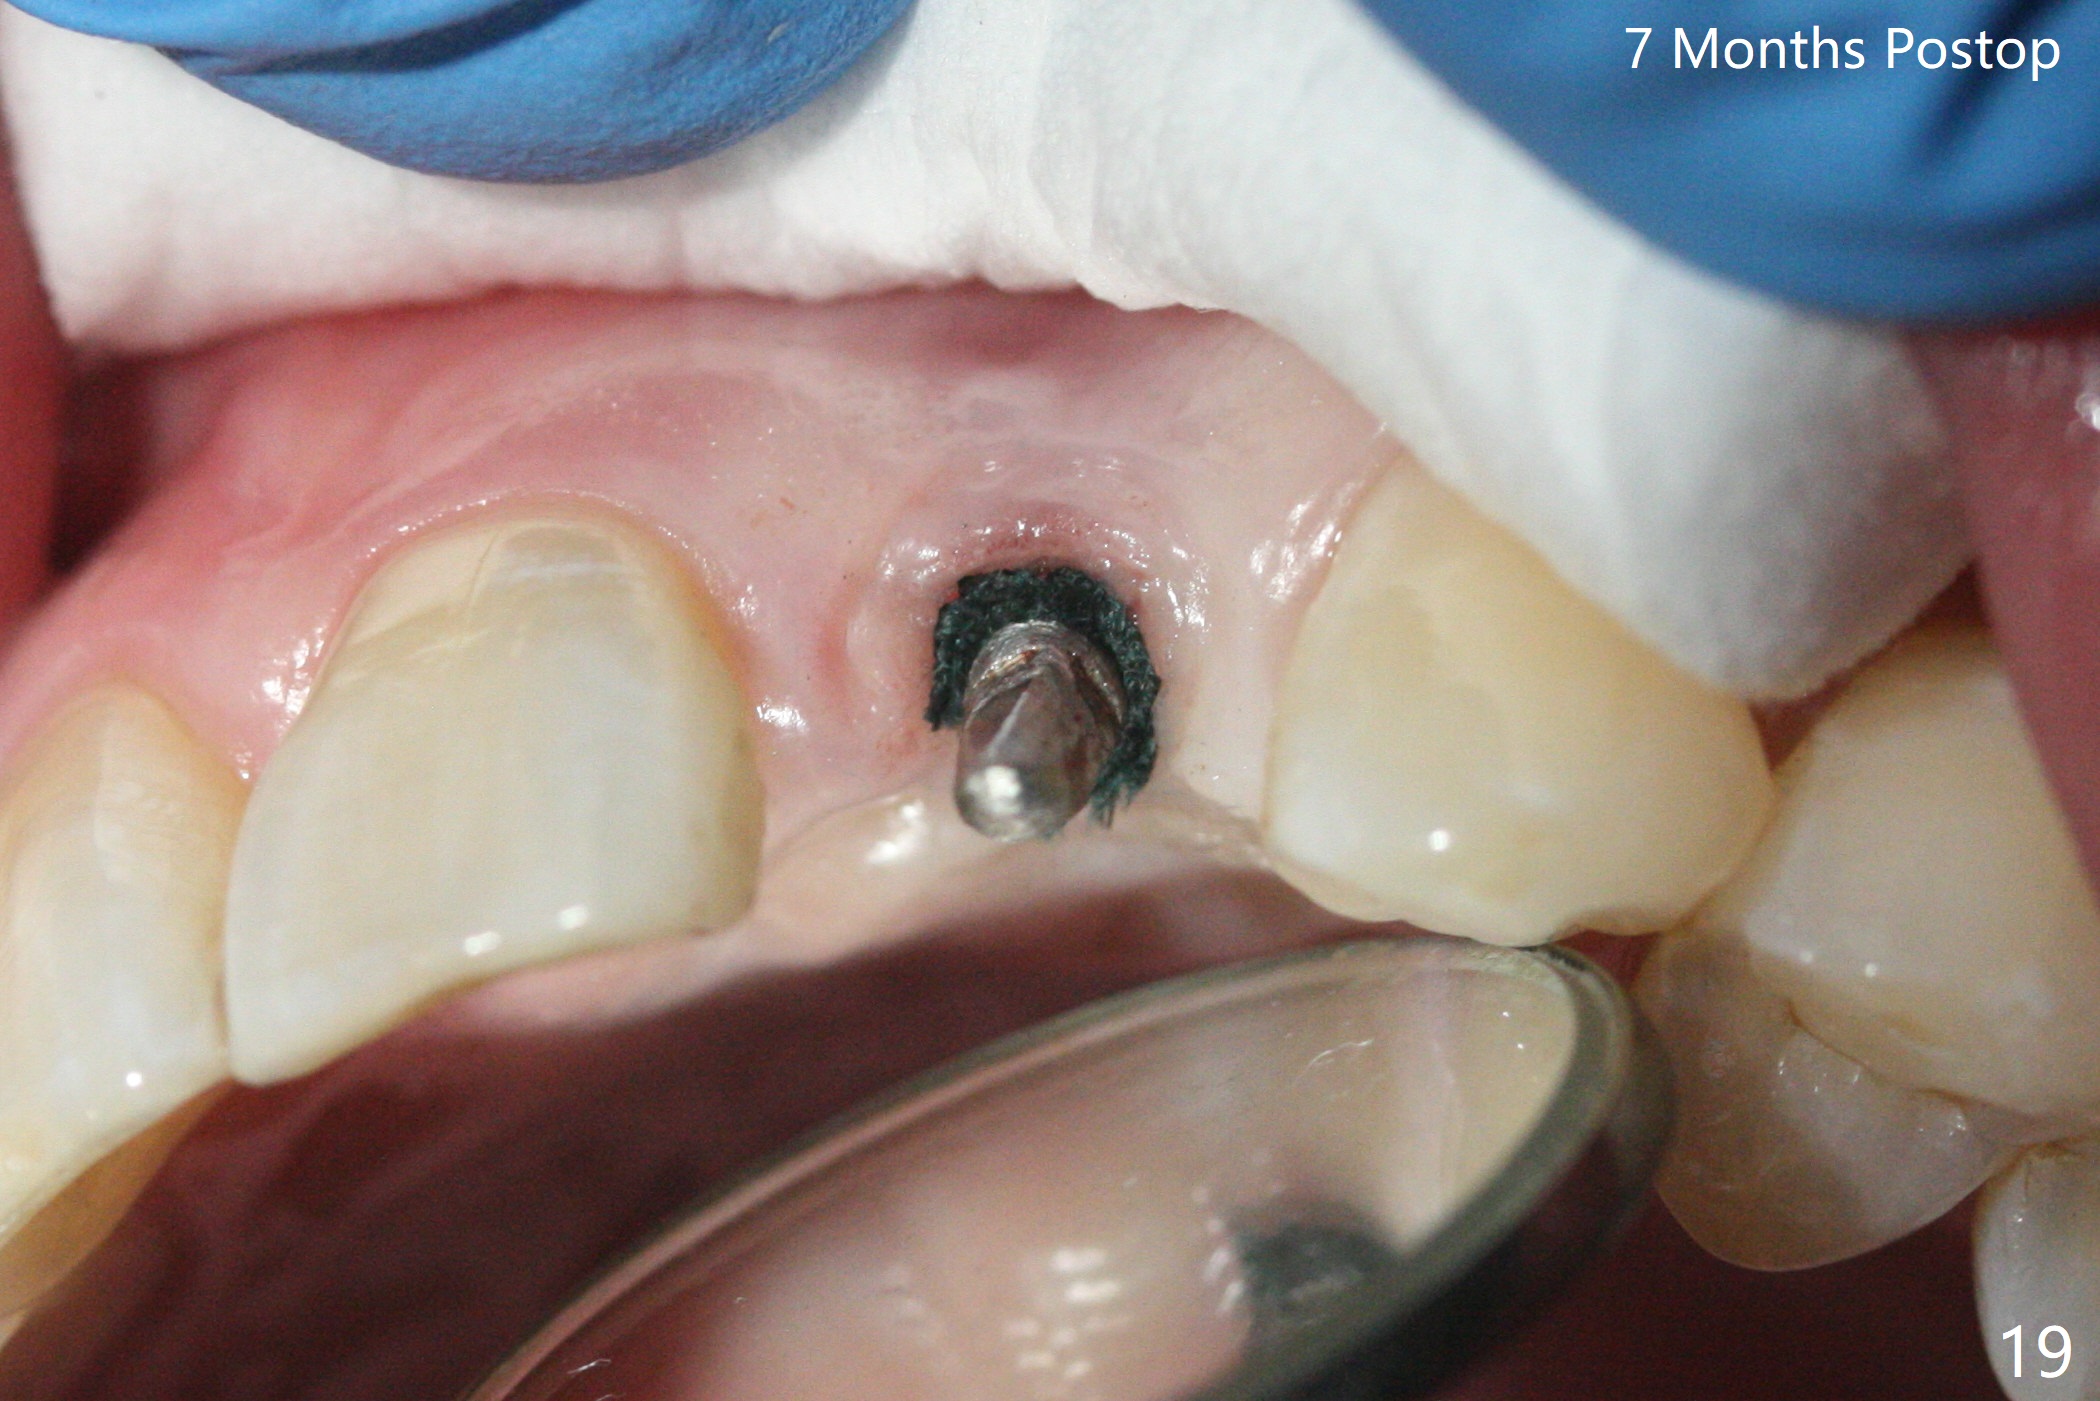

病人回来带来瘘道(图一),不过不会增加难度,病牙去除,它便自动消失。尽管颊侧骨壁完全失去,颊侧牙龈仍丰满(图二),为什么呢?第一,因为粗大牙根存在,第二两旁牙齿,牙槽骨撑着帐篷(侧切牙颊侧牙龈),第三,牙冠。为了防止术后牙龈塌陷,尽量不切开,即刻放置植体(牙根);由于前牙缘故,这次植体不能很大,所以植骨必须过度(over grafting),最后即刻制作临时牙冠,撑住牙龈。这就是所谓每个人进入角色。这个牙根有一种先天性畸形:dens in dent (图三(腭侧观):箭头)。尽管腭侧牙根畸形,腭侧骨壁吸收临床上并不严重,所以钻洞仍偏腭侧。当预定最后钻头还在钻洞时,填入大量粘性骨块(图四:*),细长植体还没有完全卡入鼻底(图五),最后好像可以(图六,七)。植体,骨粉入位(图八),最后临时牙冠出场(图九)。尽管植体小,术后一周临时牙冠仍然可以维持牙龈原有形状(emergency profile,图十:箭头(*:树脂强化牙冠固定))。图十一以不同角度显示瘘道缩小。术后三周取出有些松动的临时牙冠,骨粉虽然还没有被肉芽组织整合,但是显得正常,周围牙龈健康(图十二)。术后4个月牙龈形态正常(图十三),没有触痛;颊侧骨板轻度凹陷(图十四);骨粉仍在原位(图十五)。术后7个月骨粉仍在原位(图十五,十六,但是冠部密度减低(可能骨粉流失,需要牙周或者树脂敷料保护)),没有螺纹暴露。但是牙冠边缘暴露,说明牙龈收缩(图十七,与图十三对比),颊侧骨板仍塌陷(图十八)。插入龈线取得多个目的:修整基台边缘,取模,颊侧牙龈推向颊侧,有利于即将衬里牙冠龈缘进入龈下(图十九)。取模后牙冠边缘(图二十:<)衬里,然后修整,变窄,以便插入龈下,促进颊侧牙龈下降(图二十一,二十二)。术后8个月牙冠粘固前牙龈健康(图二十七,八),牙冠(图二十九)固位后,病人满意(图三十),咬合调整(图三十一),注意腭侧粘固粉流出通道(<)。